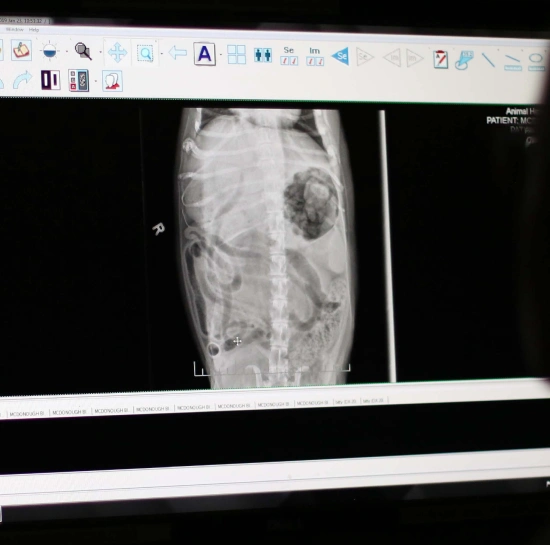

Our medical team looks to digital radiography for support in the diagnosis of countless medical conditions. Going beyond what can be seen or felt during a routine physical examination, digital radiography provides us with high-definition images of internal systems.

The high-quality images produced help us to assess the health of organs in the body, such as the heart, lungs, liver, and kidneys. Digital x-rays images are also captured to diagnose the severity of orthopedic injuries, such as breaks and fractures.

The size, shape, and position of the organs and bones in the body are meaningful. Organ size can be changed due to certain medical conditions, such as heart disease and kidney disease; And organ shape and organ position can highlight serious concerns such as intestinal blockages and tumors. Having this information available to us allows our doctors to make informed diagnosis and treatment recommendations for your pet.